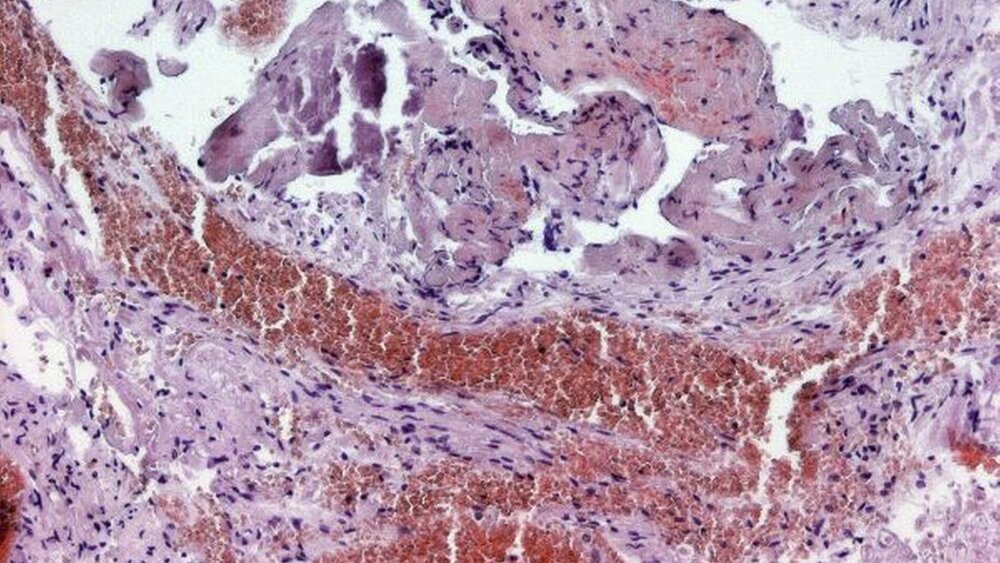

Das histologische Präparat zeigte in der van-Gieson-, in der CD34- und in der HE-Färbung (Abbildung 4) ein Bindegewebe mit zahlreichen, ektatischen Blutgefäßen. Die histopathologische Begutachtung ergab somit ein kavernöses Hämangiom.